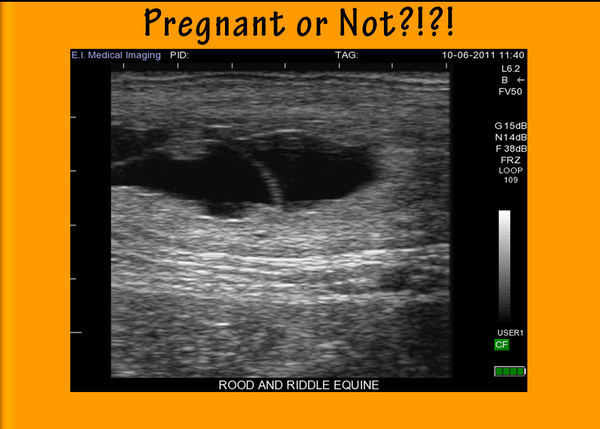

Black and white sheds light.

In our Technicolor world, your client might be surprised to see that ultrasound images are in shades of black, white and gray. You are comfortable with this monochromatic visual, but the typical horse owner may be skeptical about contemporary technology that isn’t using full, living color! Tell him that light and dark are all you really need to see on the monitor, because the intensity of the returning signal translates into a level of brightness on the screen. The more dense the tissue, the brighter the image; so fluid appears black, dense materials such as bladder stones appear bright white, and the internal organs and structures will appear varying shades of grey. This baseline information will help your client to begin to understand what the ultrasound image means.